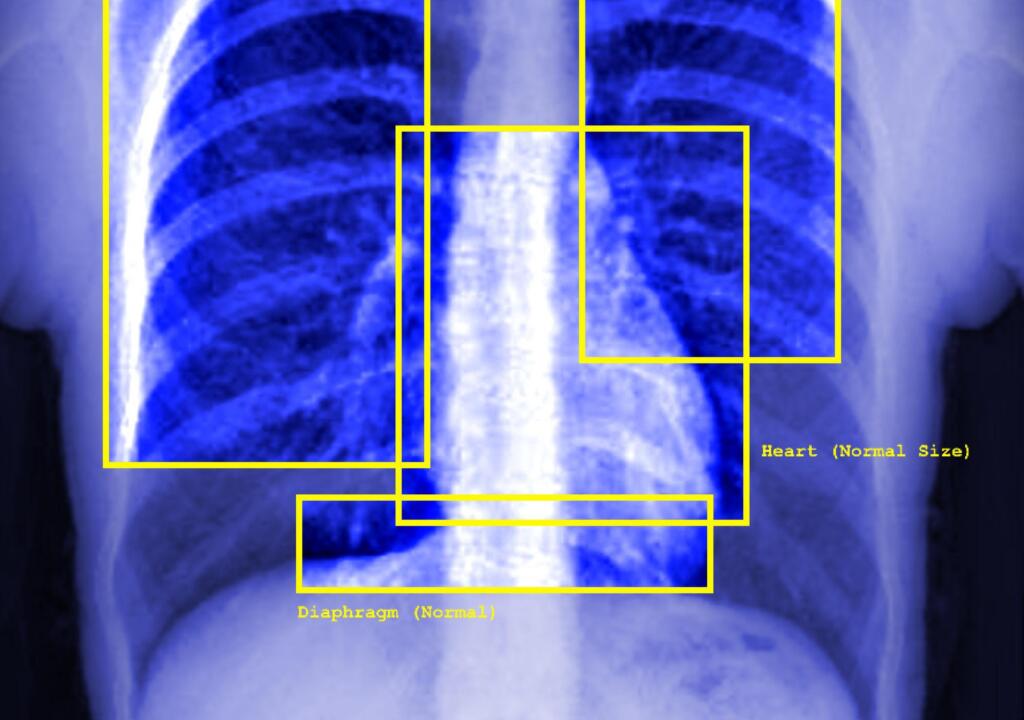

NL: Deze afbeelding toont een blauwe röntgenfoto van iemands borstkas - de ribben, de vage contouren van een hart en andere organen zijn zichtbaar. De afbeelding toont gele vierkanten rond de organen (linkerlong, luchtpijp, rechterlong, hart, middenrif) - elk met labels zoals: normaal, middenlijn, normale grootte. Rechtsonder staat in witte tekst 'geen afwijkingen gedetecteerd'.

EN: This image shows a blue xray image of a person's chest - it shows the ribs, the faint outline of a heart, and other organs. The image features yellow squares surrounding the organs (left lung, trachea, right lung, heart, diaphragm) - each of them feature labels such as: normal, midline, normal size. There is text in the right bottom corner in white which states 'no abnormalities detected'.

Afbeelding: Elise Racine / https://betterimagesofai.org / https://creativecommons.org/licenses/by/4.0/